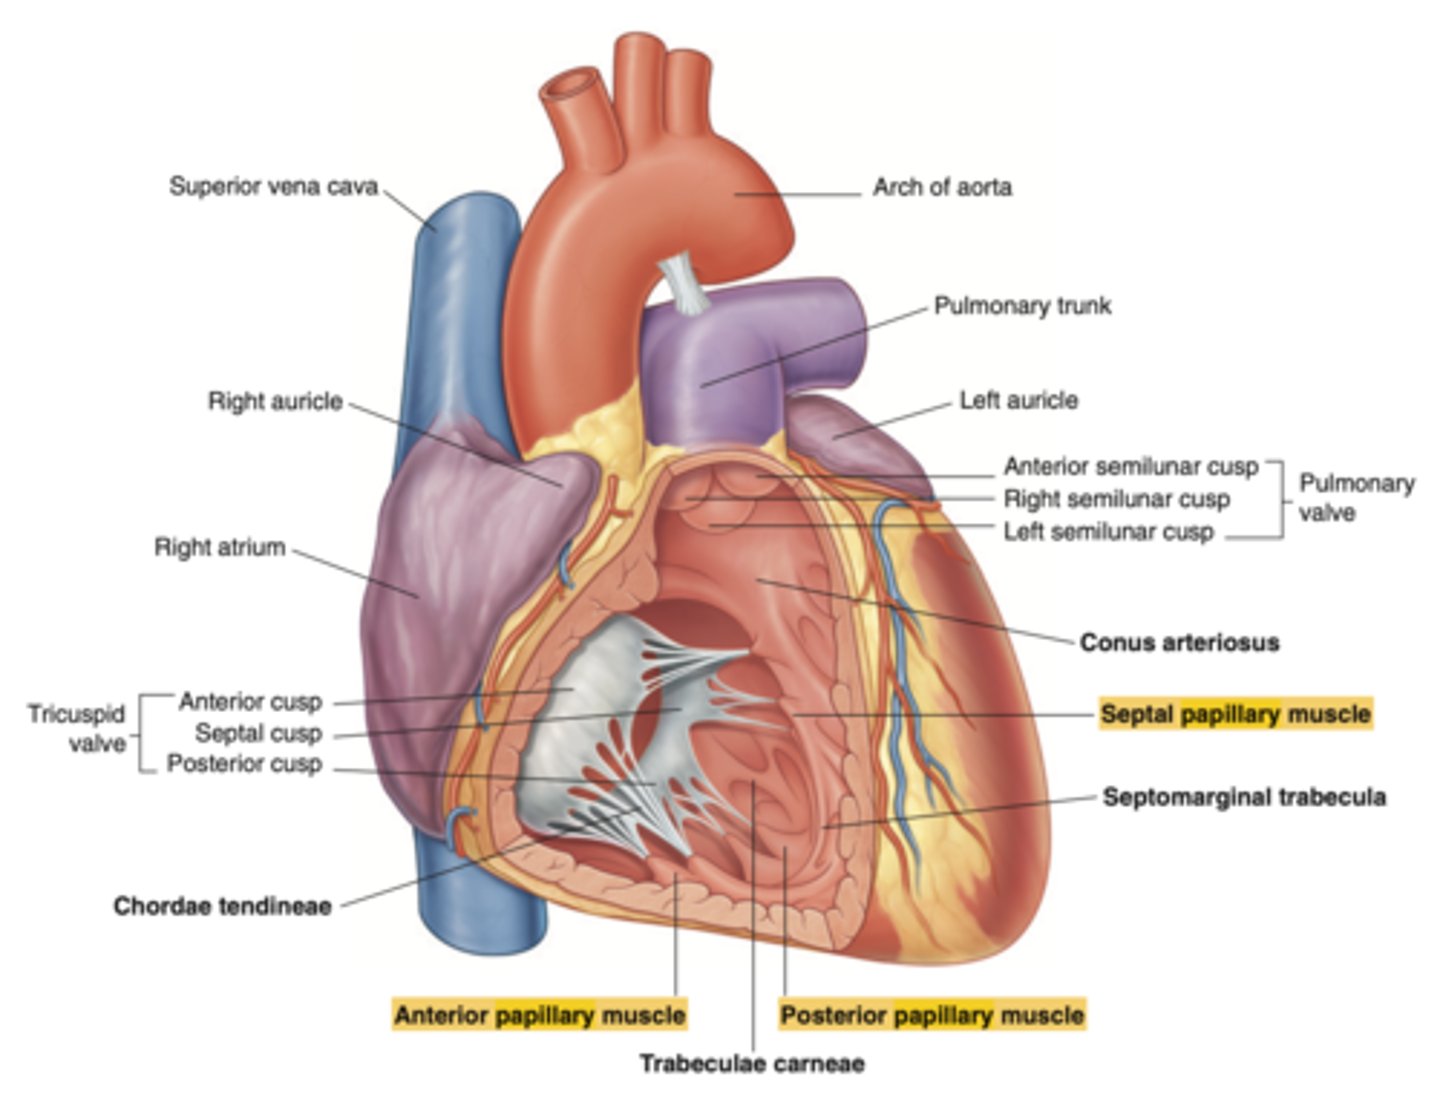

What are the valves separating atrium and ventricle?

. Tricuspid valve (right atrioventricular valve, 3 cusps)

. Mitral or bicuspid valve (left atrioventricular valve, 2 cusps)

What are the walls of the right ventricle?

. Anterior wall

. Posterior wall

. Septal wall

Right ventricle has a conical shape with 2 o 3 walls

Describe the two portions of the medial/septal face/wall of the right ventricle.

infundibulum or outflow region or conus arteriosus (smooth and membranous)

trabeculae carnae (muscular and irregular)

What are the 3 cusps of the tricuspid valve?

Anterior

Posterior

Septal

What connect the cusps of the valve a to papillary muscles in the

right ventricle?

Chordae tendinae

What is the septomarginal trabeculae (or moderator band)?

Part of the conduction system of the heart.

electrical waves pass through this band to reach the papillary muscles.

What are the positions of the pulmonary valve cusps?

Anterior

Right

Left

Why is the left ventricle wall thicker than the right?

It is 3 times thicker than the one on the right, in order to pump blood into the aorta at high pressures